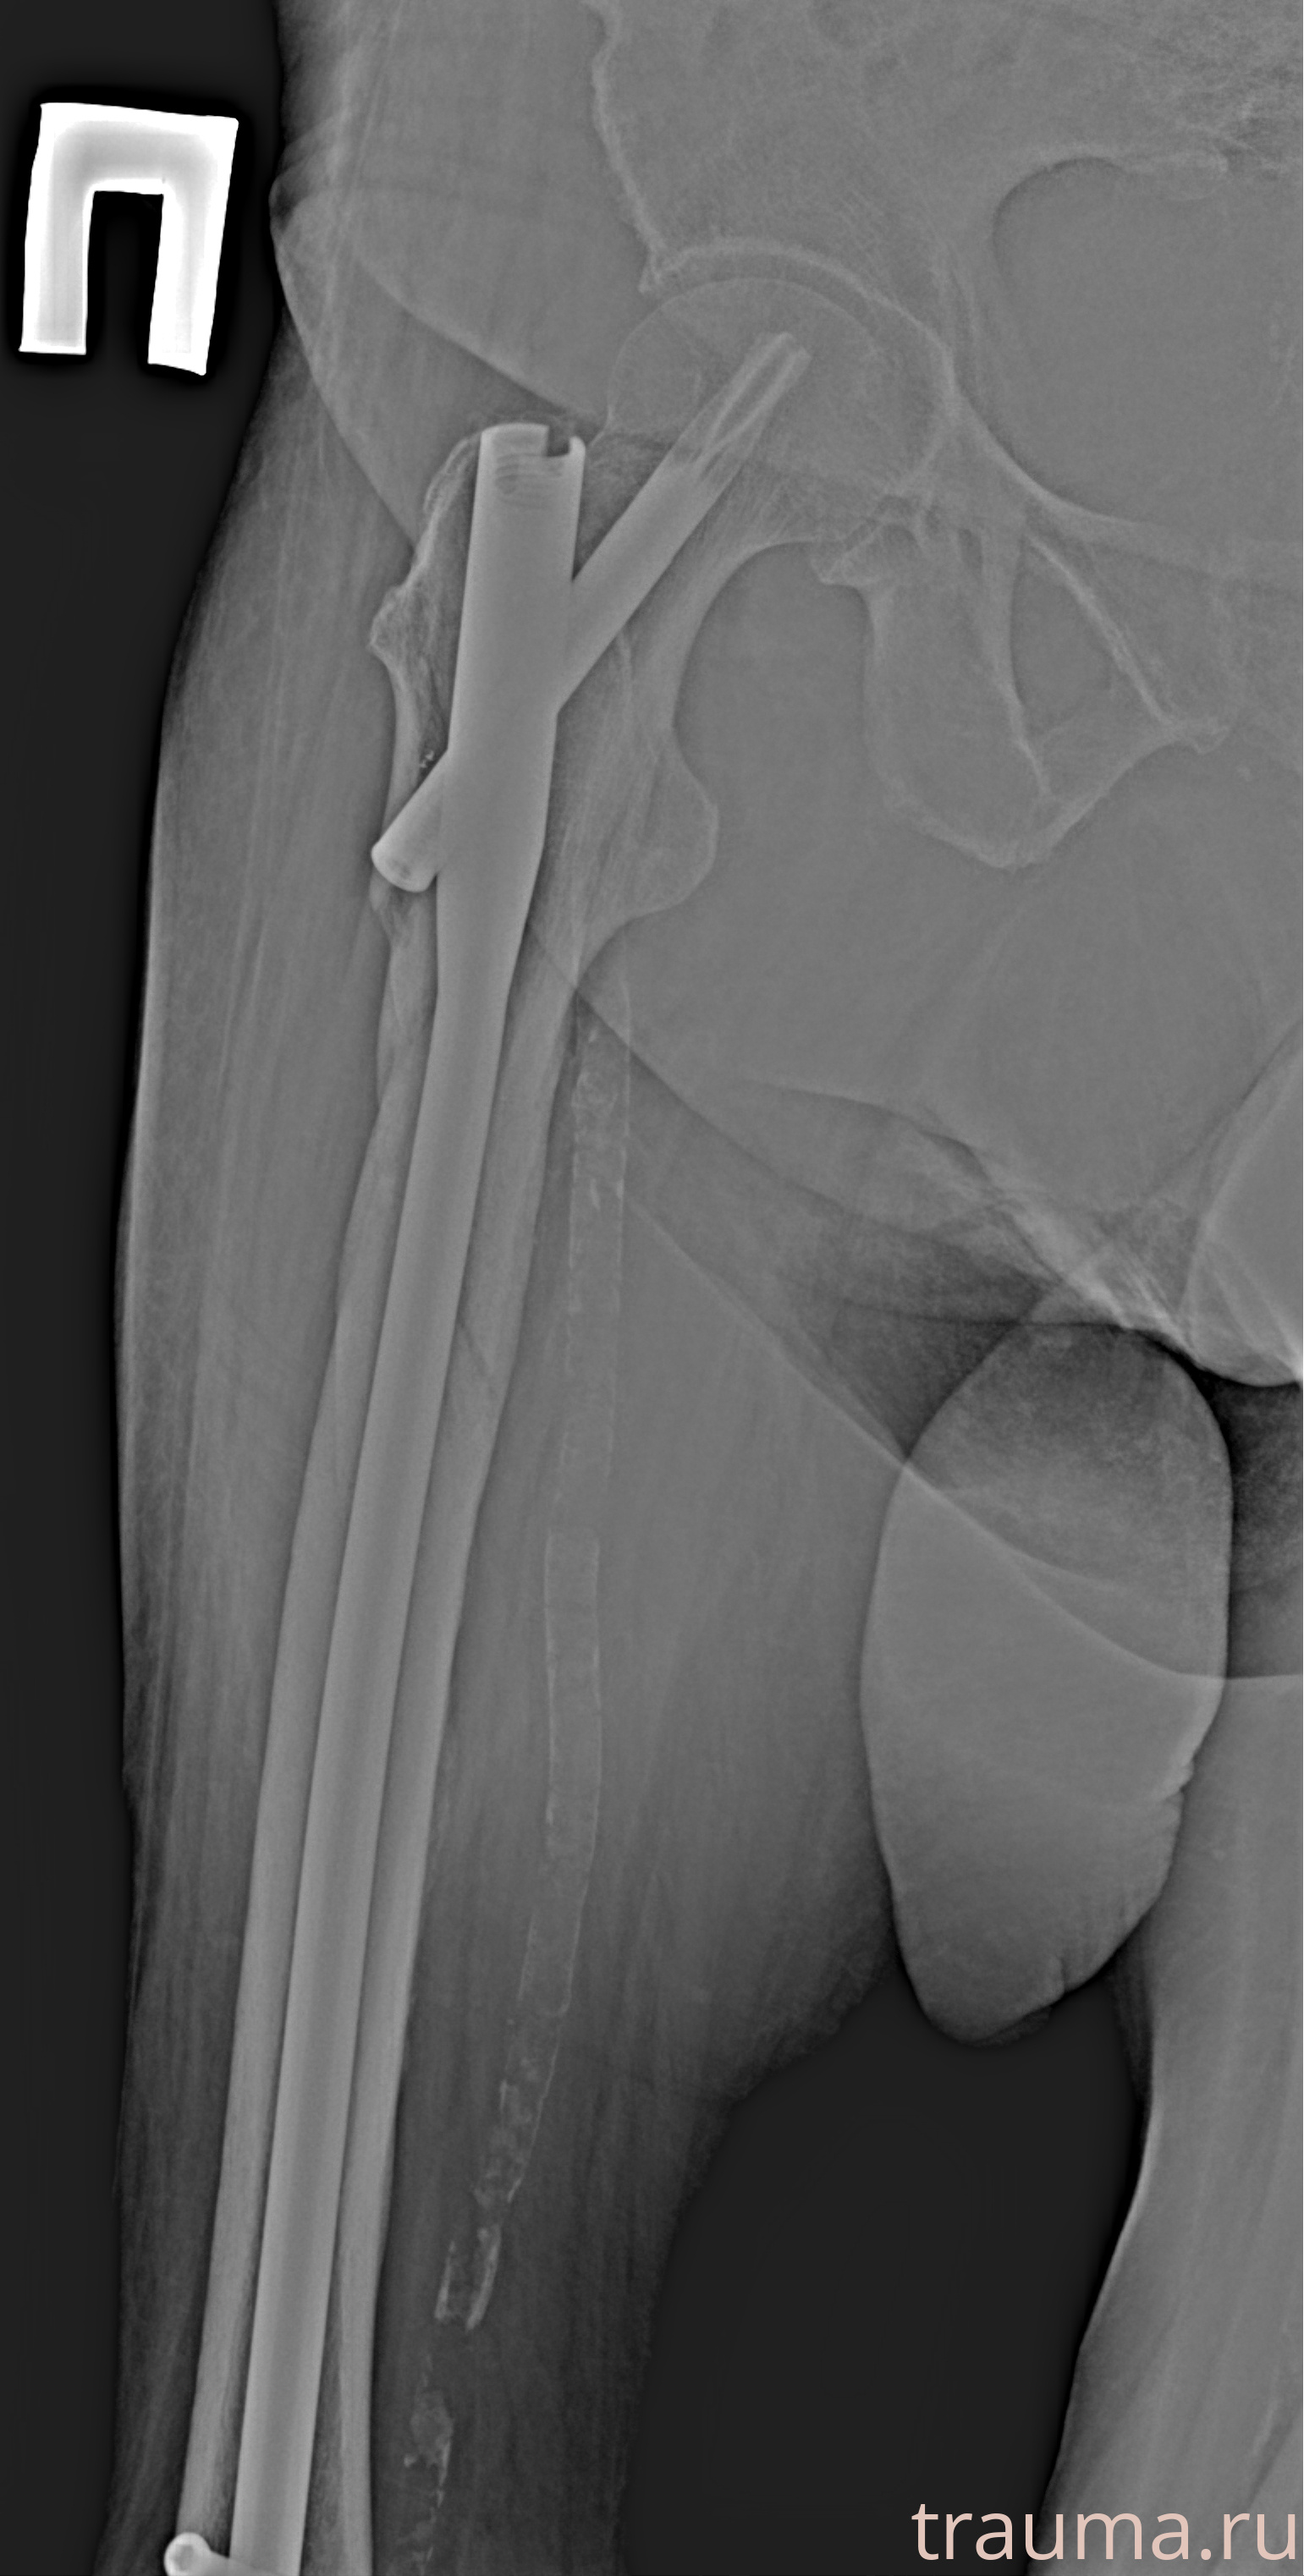

Рентгенограммы